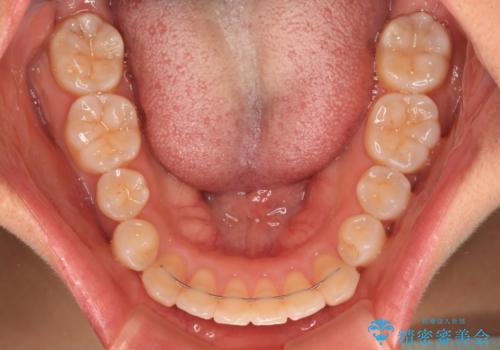

舌のトレーニングをしっかりと行ってくださり、前歯部のオープンバイトは大幅に改善されました。

もう少しでよりタイトに前歯が接触できそうでしたが、患者様がもう十分とのことで治療を終了しました。